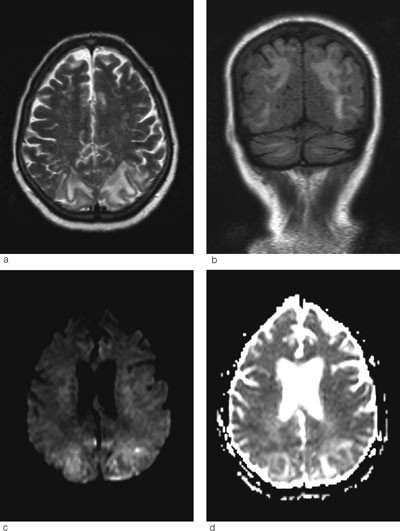

Ved MR cerebrum er det som regel karakteristiske funn ved posterior reversibel encefalopati-syndrom med vasogent ødem parietooksipitalt bilateralt (5). I uttalte tilfeller, som hos vår pasient, kan man se slike forandringer i hjernestammen og cerebellum, sjeldnere i fremre deler av cerebrum (6). T2-vektede MR-bilder og FLAIR-sekvenser er sensitive for ødem, som vises som høysignalforandringer (fig 1a-b).

Hjerneødem kan være cytotoksisk (cellulært) eller vasogent (interstitielt). Ofte foreligger det en kombinasjon. Ved hjerneinfarkt dominerer det cytotoksiske ødemet og celledød (fig 3a-b). Ved posterior reversibel encefalopati-syndrom får man et vasogent ødem som i utgangspunktet er reversibelt, men som uten behandling kan utvikles til cytotoksisk ødem og gi permanent cellulær skade. Ved hjelp av MR med diffusjonsvekting (DWI) og ADC-kart kan man skille mellom cytotoksisk og vasogent ødem. Ved MR med diffusjonsvekting er det høyt signal ved cytotoksisk ødem, mens det vanligvis er lavt signal eller ingen signalendringer ved vasogent ødem. I noen tilfeller får man likevel høyt signal ved posterior reversibel encefalopati-syndrom. Dette skyldes at DWI-resultatet er satt sammen av bidrag fra både T2-vekting og diffusjonsvekting. Høyt signal på T2 kan derfor skinne igjennom til diffusjonsbildet. Dette var også tilfellet hos vår pasient (fig 1c). Det er derfor viktig med ADC-kart, hvor bidraget fra T2 er fjernet og man får et rent diffusjonsbilde (7). ADC-kart viser alltid lavt signal ved cytotoksisk ødem og høyt signal ved vasogent ødem, som ved posterior reversibel encefalopati-syndrom (fig 1d).

Det ble vurdert ytterligere behandling av de mulige utløsende årsakene, men blodtrykket, infeksjons- og nyreprøver normaliserte seg imidlertid spontant det første døgnet, slik at ingen videre behandling ble gitt. Pasienten ble raskt bedre, og etter noen dager fikk hun gradvis synet tilbake. Paresene bedret seg langsomt, og hun var oppegående etter noen uker. Ved kontroll etter fire måneder var hun helt symptomfri, og det var ingen patologiske funn ved nevrologisk undersøkelse. MR cerebrum viste at ødemforandringene hadde gått helt tilbake (fig 2a-b).